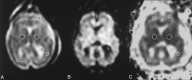

F<sc>ig</sc> 1.

Fig 1.

Representative case (fetus 10 in Table). A, T2-weighted echo-planar image (b = 0 s/mm2), B, corresponding DW image, and C, resultant trace ADC map illustrate typical ROIs (circles in A and C) traced on an axial section at the basal ganglia level.